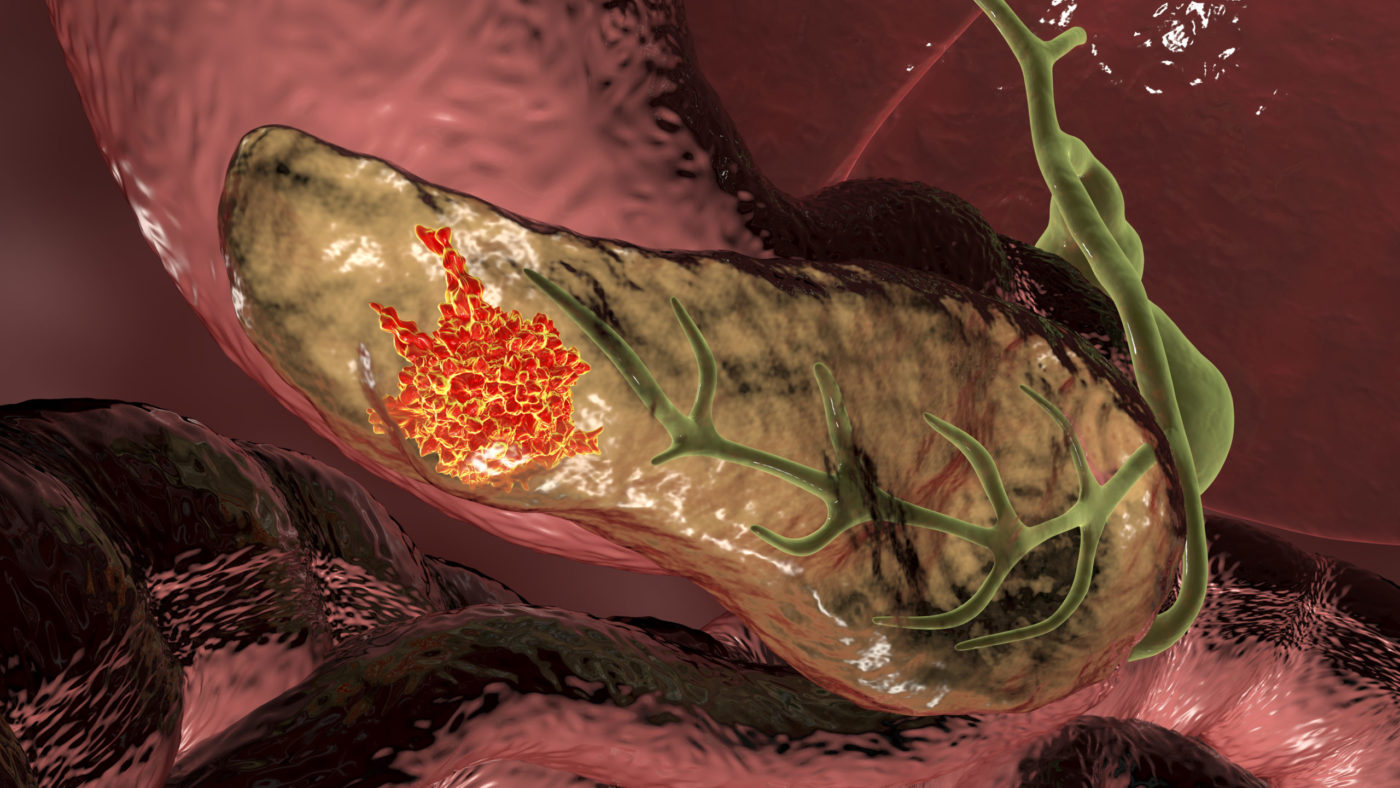

سرطان البنكرياس.. 05 “علامات” لتحذيرك من أشرس أنواع السرطان

يصاب الكثير من الناس بسرطان البنكرياس، الذي يعد واحدا من أشرس أنواع السرطان وترتبط به نسب وفيات مرتفعة، وذلك لأن أعراضه لا تُكتشف بسهولة، مما يؤدي لتأخر التشخيص.

ووفقا لجمعية السرطان الأميركية، فإنه سيتم تشخيص أكثر من 62 ألف أميركي بسرطان البنكرياس في عام 2022، وسيموت ما يقرب من 50 ألفا بسببه.

وأهم عوامل الخطر للإصابة بسرطان البنكرياس، تشمل التدخين وزيادة الوزن والإصابة بداء السكري أو التهاب البنكرياس المزمن والتعرض للمواد الكيماوية السامة. كما يلعب تاريخ العائلة والجنس والعرق والوراثة أيضا دورا في الإصابة بسرطان البنكرياس.

وعلى الرغم من صعوبة اكتشاف أعراض سرطان البنكرياس، فإن هناك أشياء معينة يراها الأطباء تتكرر عند تشخيص المرض، ولا ينبغي تجاهلها، تشمل:

1- اليرقان

الأطباء حذروا من أن اصفرار الجلد والعينين هو من أكثر علامات سرطان البنكرياس شيوعا.

وفقا لجمعية السرطان الأميركية، غالبا ما يكون اليرقان هو أول علامة على المرض، خاصة إذا انتشر السرطان من البنكرياس إلى الكبد.

2- مشاكل الجهاز الهضمي وفقدان الوزن

قد تكون مشاكل الجهاز الهضمي تكون علامة تحذيرية لسرطان البنكرياس، خاصة إذا أصيب الشخص بالإسهال.

مركز البنكرياس في قسم الجراحة بجامعة كولومبيا، أوضح أن “الإسهال ينتج عندما لا يتم امتصاص العناصر الغذائية الموجودة في الطعام بشكل صحيح”.

إنزيمات البنكرياس مسؤولة عن هضم الأطعمة الدهنية، وإذا كان الورم يسد قناة البنكرياس، فإن عدم كفاية عصارة البنكرياس في الأمعاء يمكن أن يؤدي إلى سوء الامتصاص والإسهال.

طبيب الأورام هينز لينز: “إذا لم تتدفق عصائر البنكرياس، فإن عملية الهضم لا تكتمل، مما قد يؤدي إلى الانتفاخ، وقلة الشهية وفقدان الوزن، عندما لا تحاول إنقاص الوزن”.

إذا كان الورم يضغط على المعدة، فقد يعاني الشخص أيضا من الغثيان والقيء.

3- السكري

يرتبط مرض السكري ارتباطا وثيقا بسرطان البنكرياس، لكن الخبراء ما زالوا غير متأكدين من الصلة المباشرة، وكيف يؤثر أحدهما على الآخر.

أستاذ أمراض البنكرياس في كلية الطب بجامعة أوكلاند، ماكس بتروف، قال: “الأشخاص الذين يعانون من السمنة ومرض السكري، غالبا ما يكون لديهم مستويات عالية من الأنسولين، ويمكن للأنسولين أن يحفز انقسام الخلايا. وبمرور الوقت، يمكن أن تعزز المستويات العالية من الأنسولين تكوين الورم”، لافتا إلى أنه “لم يتم إثبات ذلك، لكنها نظرية”.

4- وجع بطن

قد يكون ألم البطن علامة على الإصابة بسرطان البنكرياس، ربما لأن الورم يضغط على العمود الفقري ويسبب إزعاجا شديدا.

الباحث في سرطان البنكرياس، شبهام بانت، قال: “مع نمو الأورام في البنكرياس، فإنها غالبا ما تضغط على أجزاء أخرى من الجسم، مما قد يكون مؤلما للغاية”.

مركز أبحاث السرطان في المملكة المتحدة، أوضح أن الألم يمكن أن يبدأ في منطقة المعدة وينتشر حول الظهر، ويكون أسوأ عندما يكون الشخص مستلقيا، ويتحسن إذا جلس إلى الأمام. ويمكن أن يكون أسوأ بعد الوجبات.

5- التدخين

يعد التدخين عامل خطر رئيسي للكثير من الحالات الصحية، وسرطان البنكرياس أحدها.

دراسات سريرية متعددة أظهرت أن تدخين التبغ، خاصة السجائر، يزيد من خطر الإصابة بأمراض البنكرياس، مثل التهاب البنكرياس والسرطان.

غالبا ما تم ربط تدخين التبغ كعامل مشارك مع تعاطي الكحول، في زيادة خطر الإصابة بأمراض البنكرياس، في الدراسات، ومع ذلك، فإن إدراج المدخنين الذين لا يشربون الكحول في بعض هذه الدراسات، أبرز أن تدخين السجائر يمكن أيضا اعتباره عامل خطر مستقل.

وقال الطبيب جوزيف هيرمان، إن “الأشخاص الذين يدخنون أكثر عرضة للإصابة بسرطان البنكرياس بمرتين، مقارنة بمن لا يدخنون”.